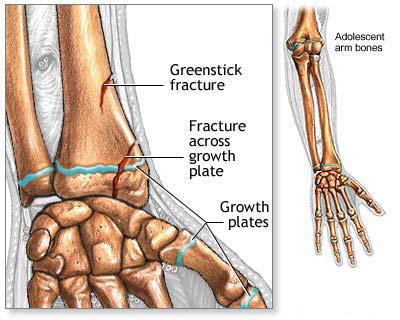

Fracturile diafizare ale oaselor antebratului